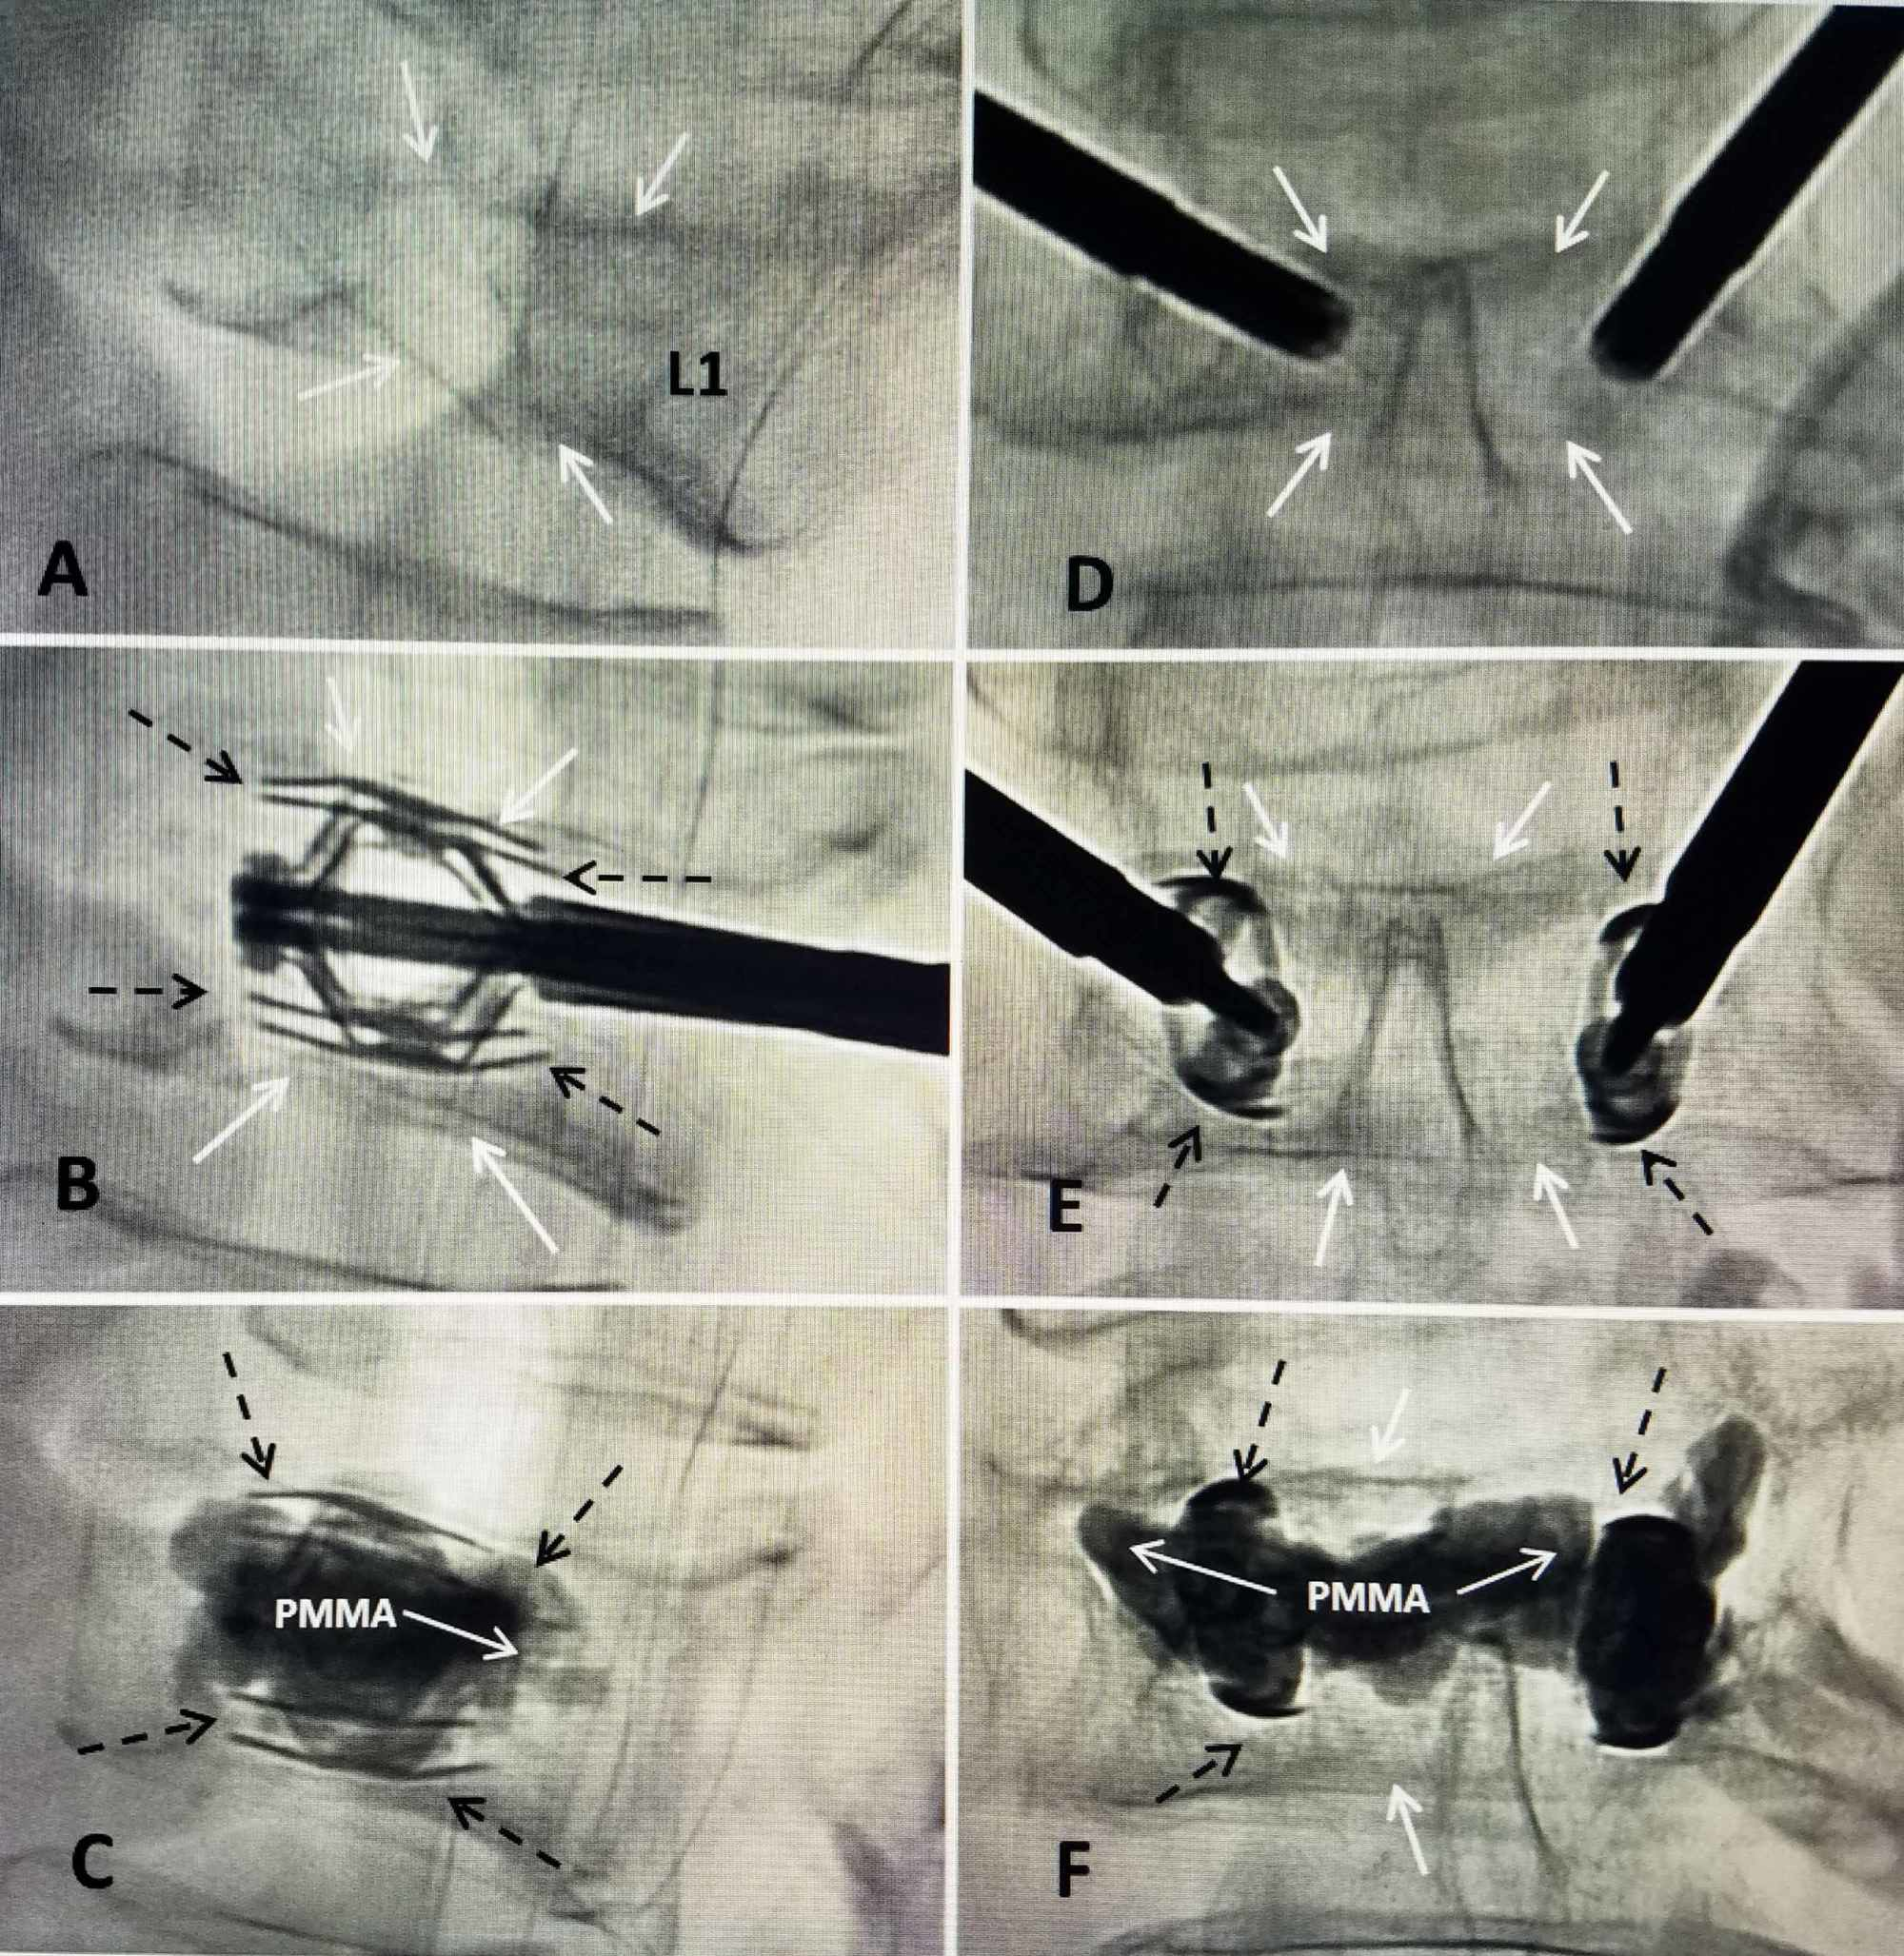

Intraoperative radiographs (a) expansion of SpineJack implant; (b Spine Jack Procedure the spinejack system allows you to take full control of implant placement and expansion. Pain doesn't have to be permanent. spine jack kyphoplasty is a minimally invasive surgery that uses a titanium implant to restore height and. the spinejack ® system is indicated for use in the reduction of mobile spinal fractures that may result from osteoporosis,. Spine Jack Procedure.

Intraoperative radiographs (a) expansion of SpineJack implant; (b Spine Jack Procedure Each kit contains the appropriate. spinejack is a system that treats osteoporotic vertebral compression fractures, the most common cause of severe back pain. spinejack system procedure | interventional spine. the spinejack ® system is indicated for use in the reduction of mobile spinal fractures that may result from osteoporosis, trauma. spine jack kyphoplasty is a minimally. Spine Jack Procedure.